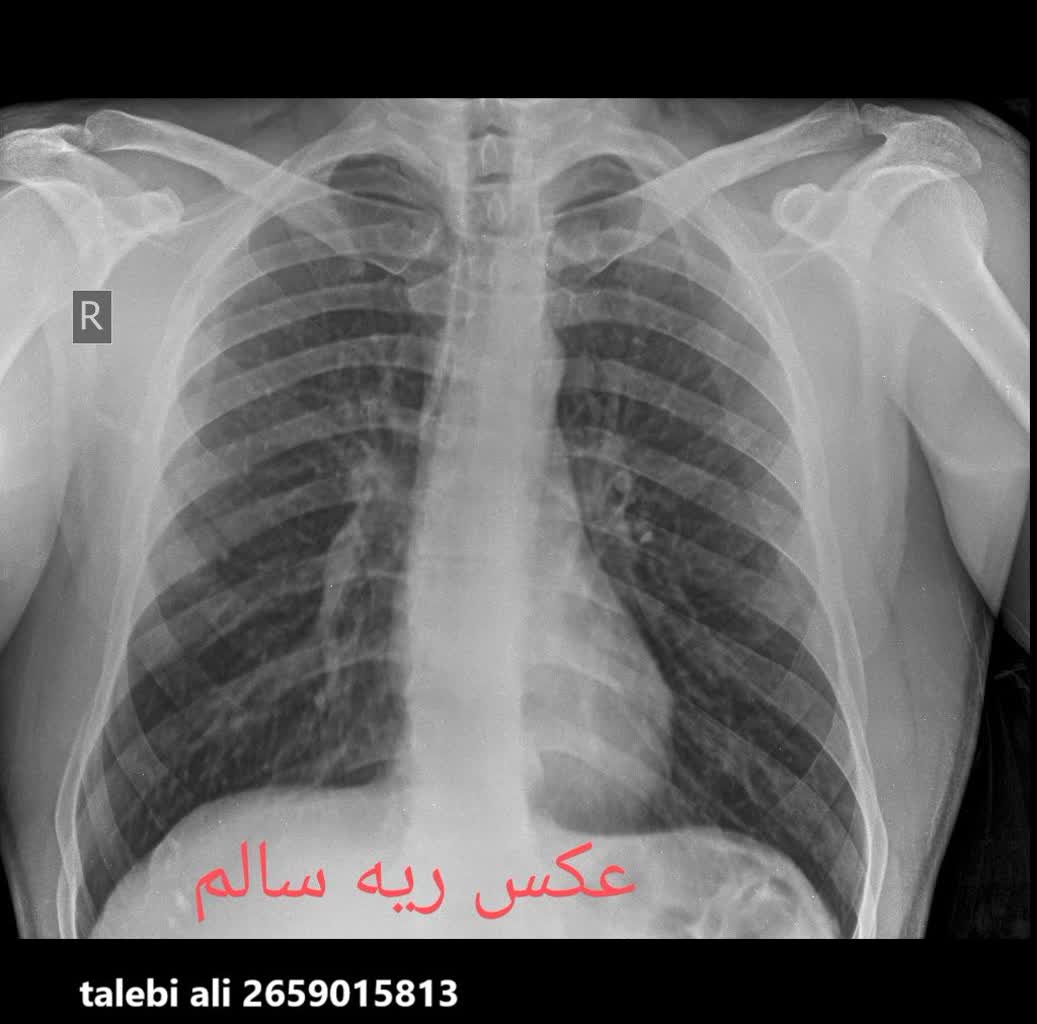

مقایسه عکس ریه سالم و ناسالم

در عکس ریه سالم و ناسالم، تفاوتها معمولاً با چشم غیرمسلح نیز مشهودند. ریه سالم تصویری یکنواخت و شفاف دارد، با خطوط ریوی طبیعی و بدون سایه یا توده. در مقابل، ریه ناسالم ممکن است سایههای غیرطبیعی، نواحی سفید شده (indicative of consolidation)، خطوط پررنگتر ناشی از فیبروز یا تودههای نامنظم را نمایش دهد. تشخیص این تفاوتها توسط پزشک رادیولوژیست، نیاز به تجربه و تجهیزات باکیفیت دارد، چیزی که در خدمات رادیولوژی ریه در منزل تهران و رادیولوژی ریه در منزل کرج فراهم شده است.